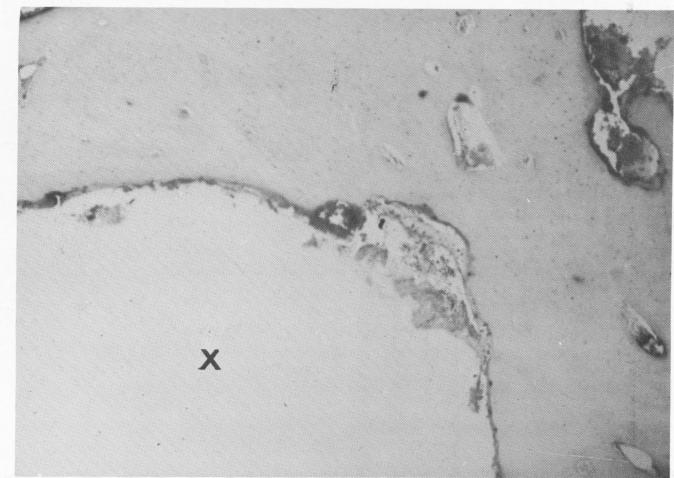

Fig. 4-54. Beyond the fibrous tissue lies bone, which follows the shape of the implant site (X).